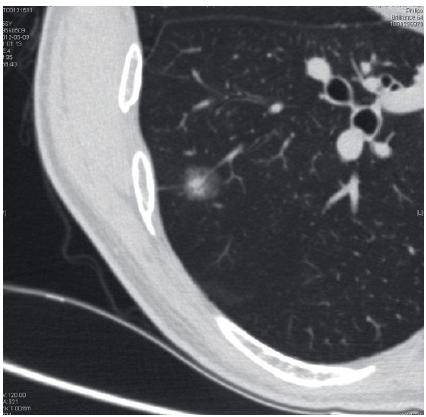

(图 4)56 岁女性,体检发现右下肺结节影 5 个月。无吸烟史。胸部 CT 影像学所见(2011 年 9 月):右肺下叶结节状影,直径约10 mm,边界清楚与胸膜紧邻,内部密度均匀为实性结节。

5 个月后随访 CT 薄层重建可见轻度分叶征象。遂剖胸探查。

病理:右肺下叶浸润性腺癌,乳头状腺癌为主,中分化,肿瘤大小8 mm×7 mm×7 mm。 医学百科网 | YxBaike.Com

| 图 4 右下叶实性小结节伴分叶。手术病理:乳头状腺癌 |